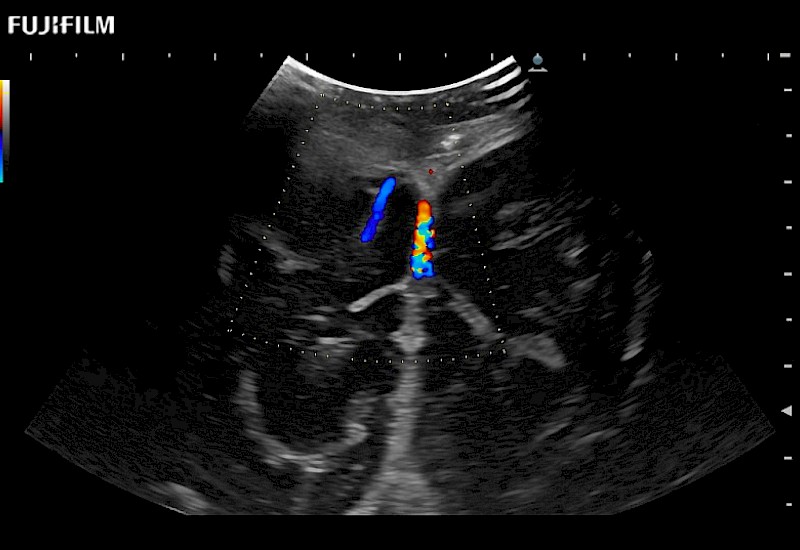

The world's only phased array burr-hole transducer that is ideal for scanning during burr-hole guidance procedures.

Main Specifications: